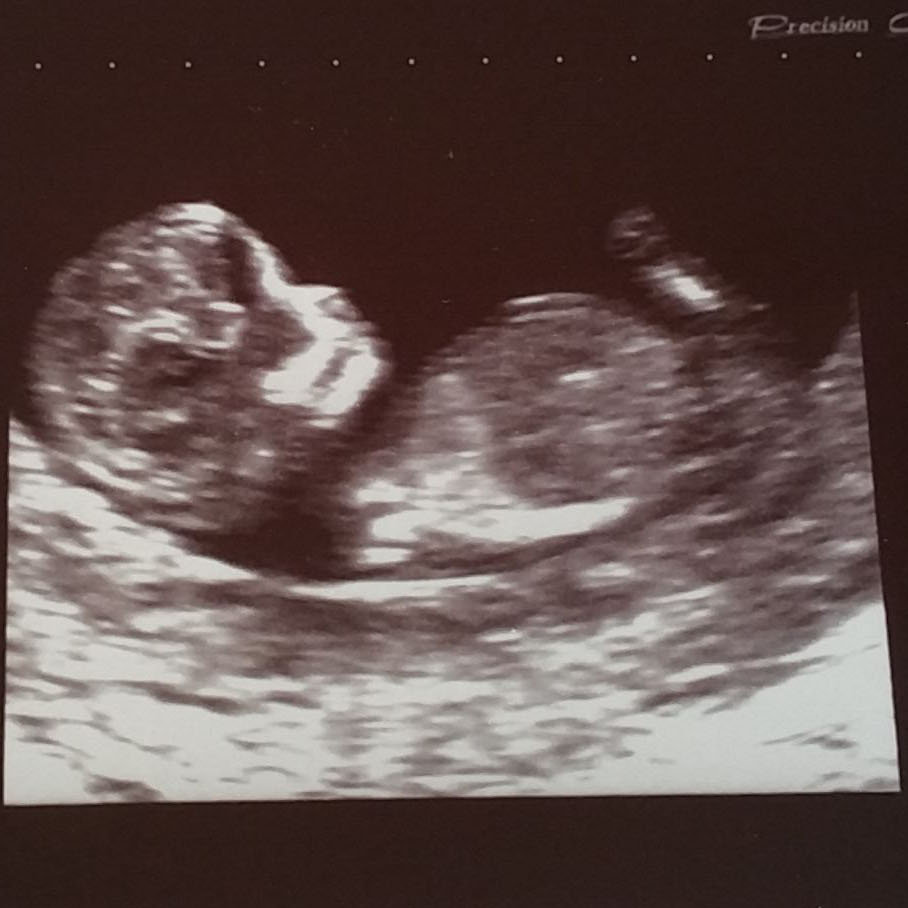

Any guesses please :o)Attachment 25895

Maybe a slight hint of a girly nub there, and a girly skull (not reliable though). But very difficult to say from this pic, sorry.

Quote: Originally Posted by Claire33 Maybe a slight hint of a girly nub there, and a girly skull (not reliable though). But very difficult to say from this pic, sorry. Thanks :) I've had a couple of people say they can't see a nub, thankyou though :)